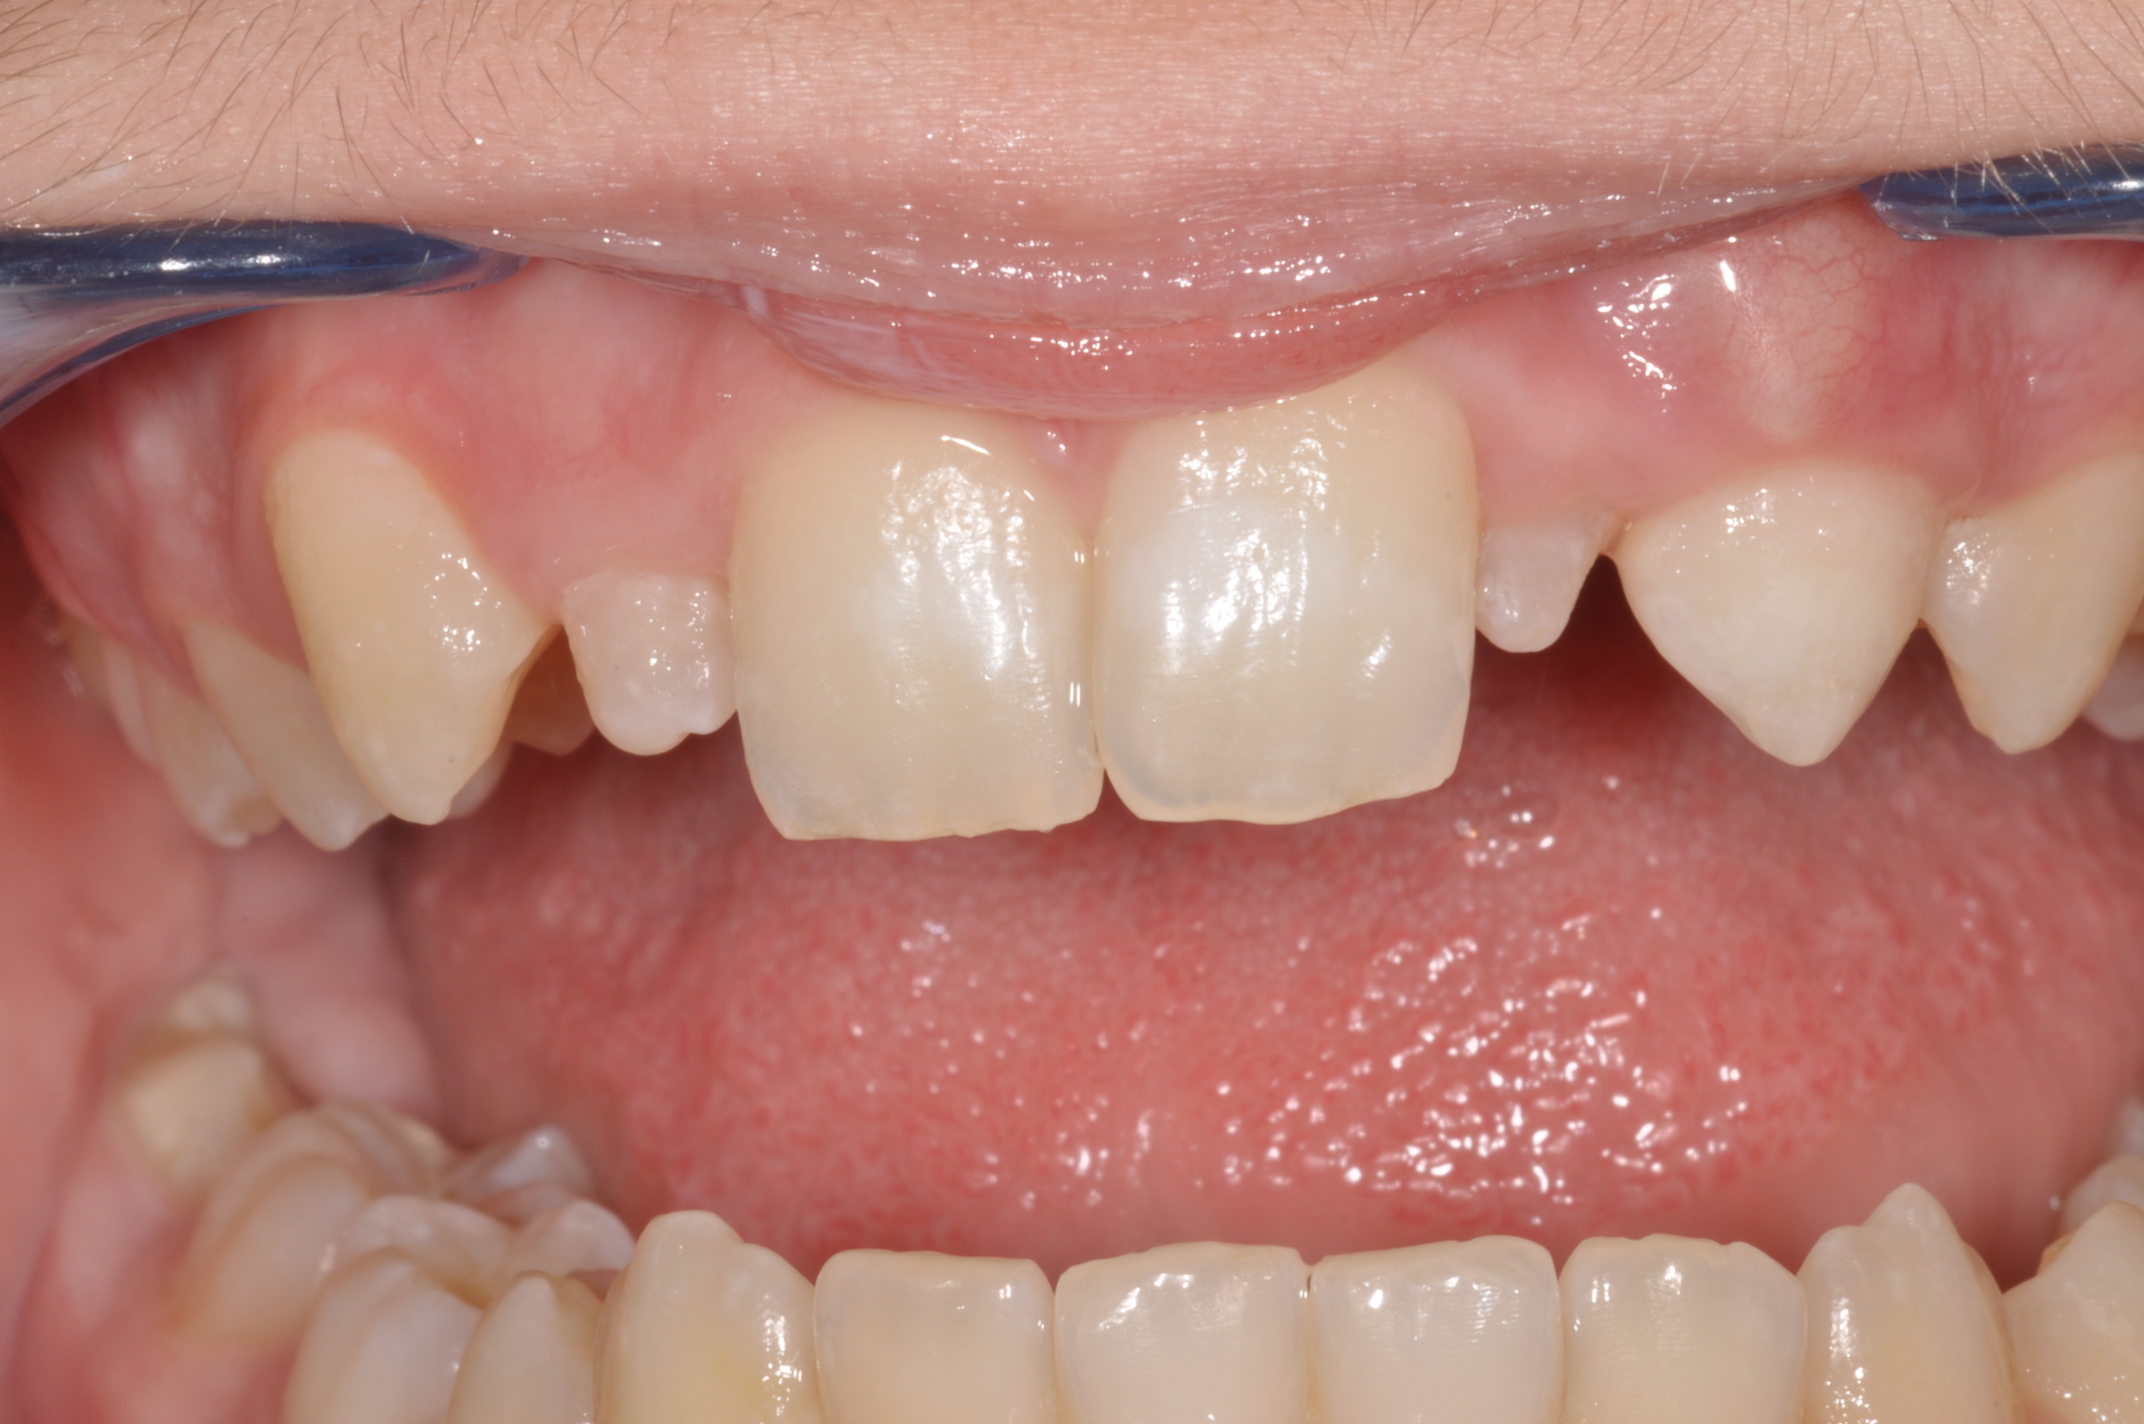

Situation nach Sturz

Vorher: Situation nach Sturz

Ästhetische Sofort-Rekonstruktion mit Microglass-Composite

Nachher: Ästhetische Sofort-Rekonstruktion mit Microglass-Composite